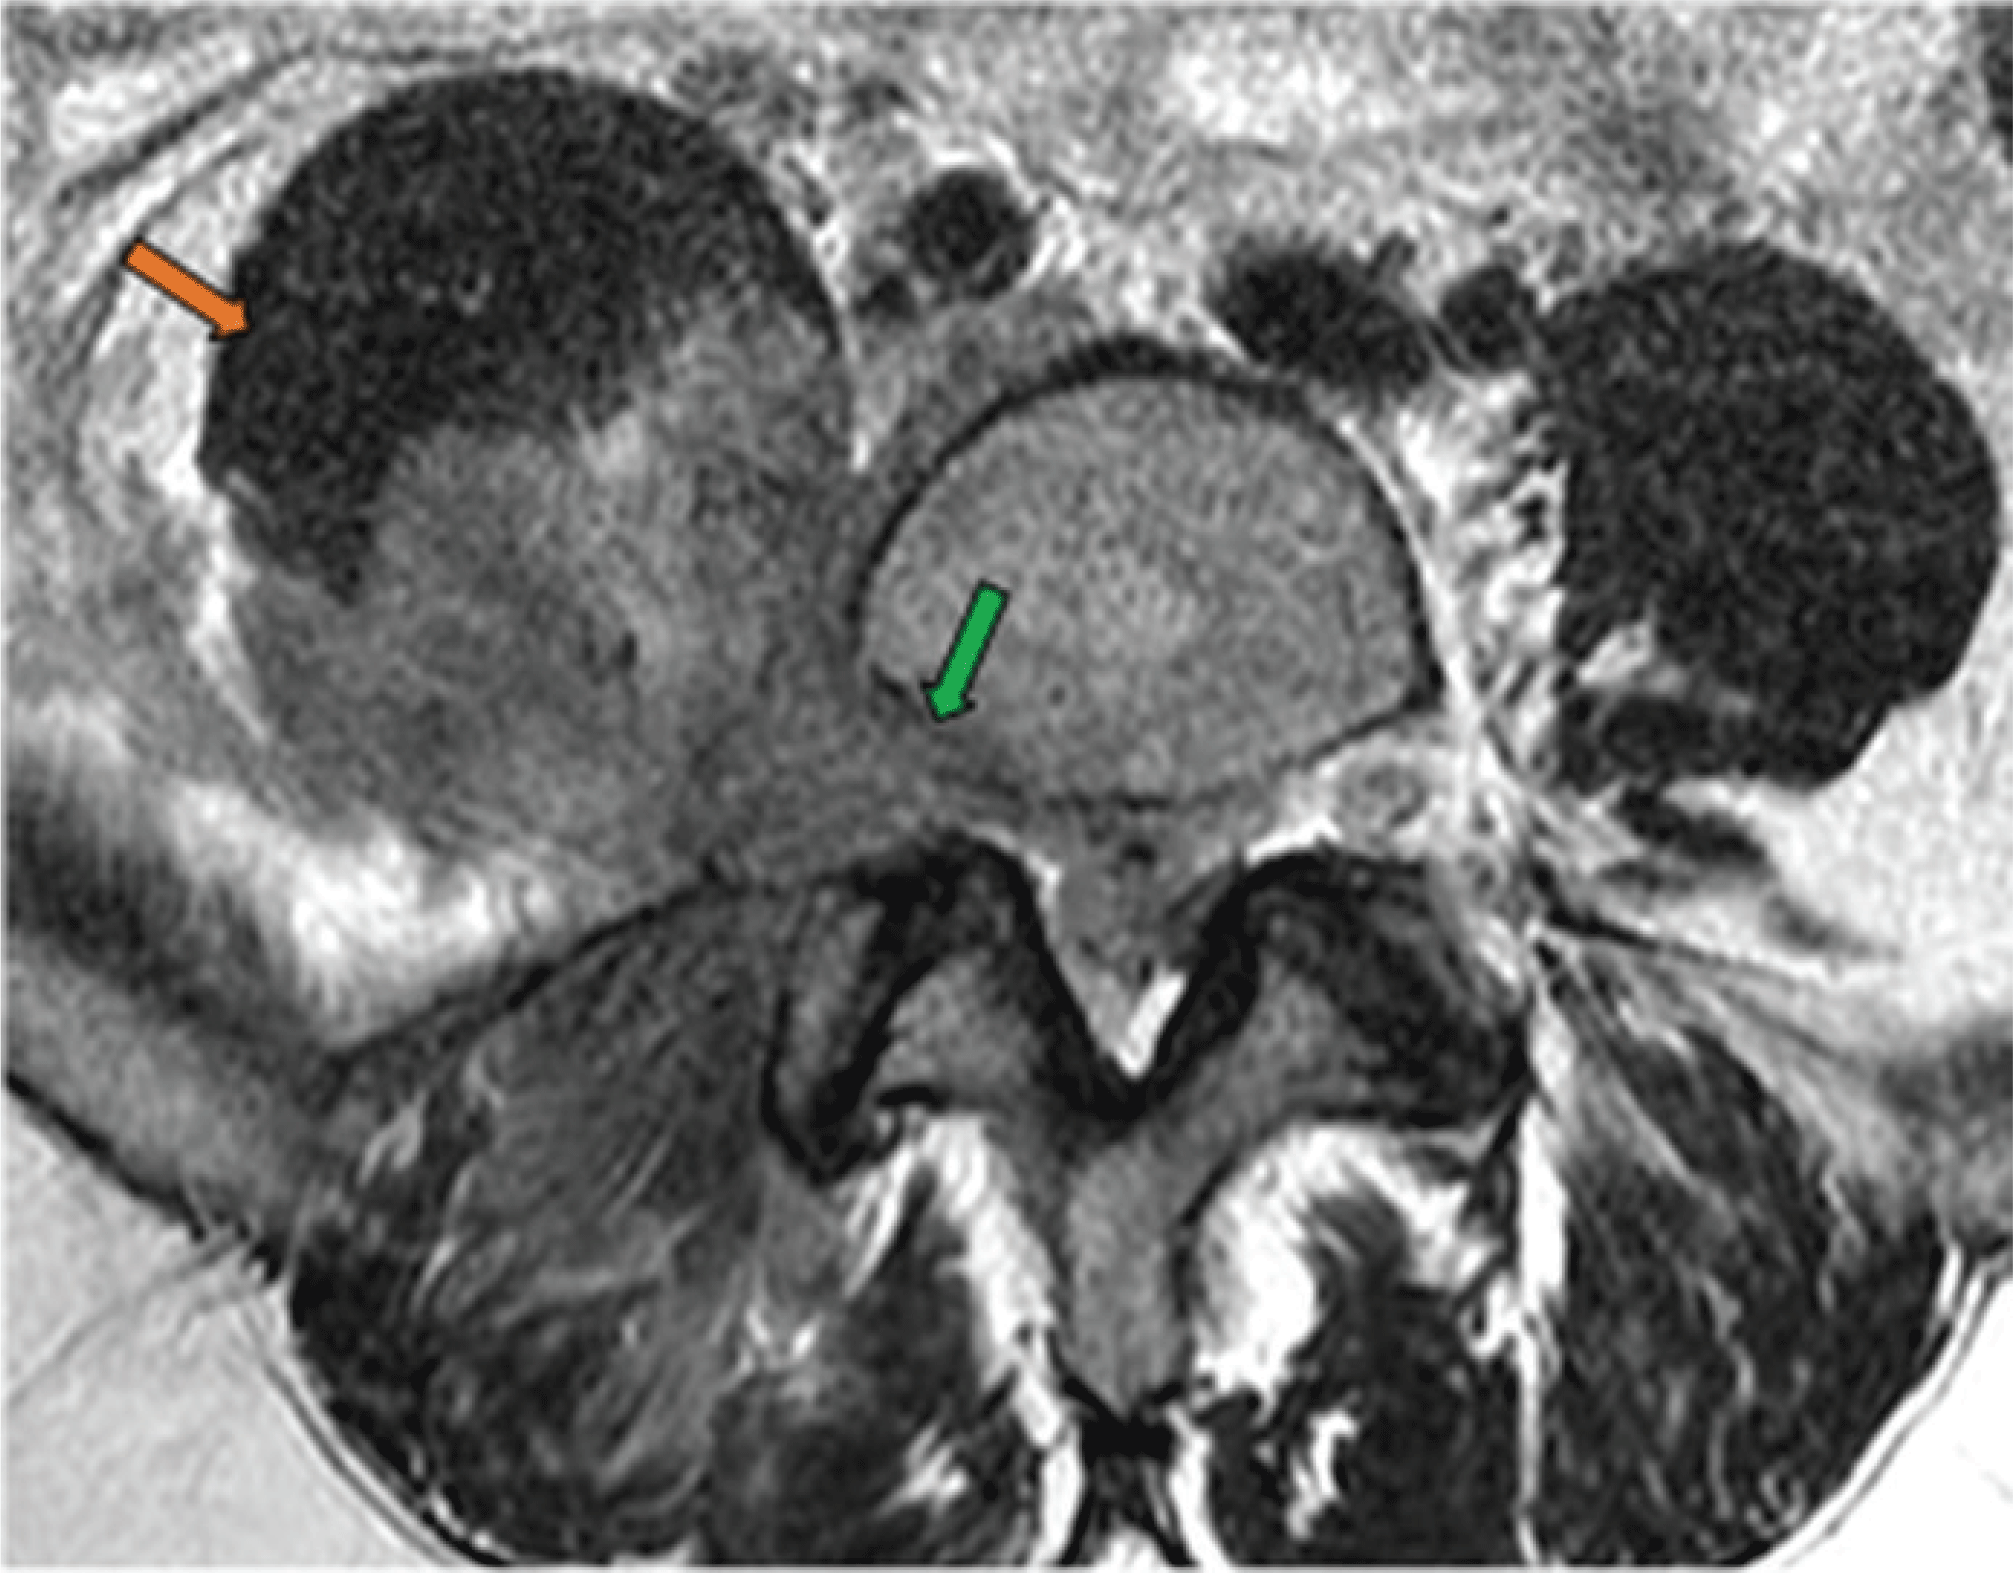

Pain Related Disease States: Lumbar Disk Herniation